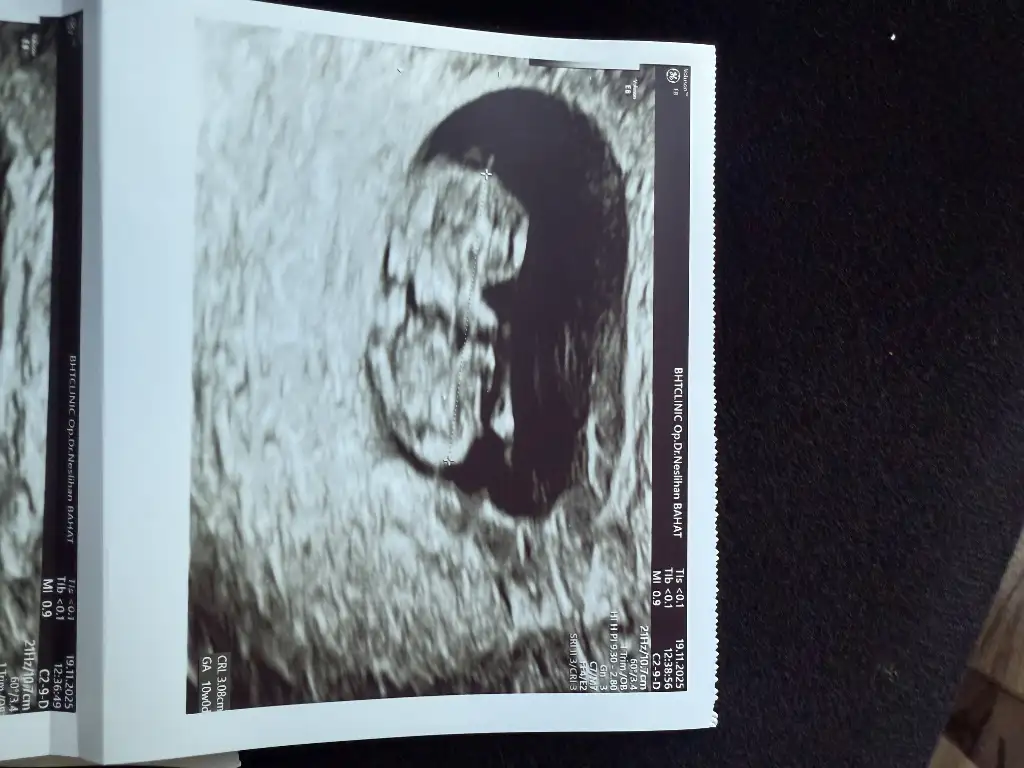

Kızlar doktordan gelıyorum 10hafta bıttı cok sukur kanama alanı hala mevcut 2hafta sonra ense kalınlıgı ıcın cagırdı sızce cınsıyet ne olabılır

Eklentiler

• IMG_4810.webp

IMG_4810.webp

40,2 KB · Görüntüleme: 27